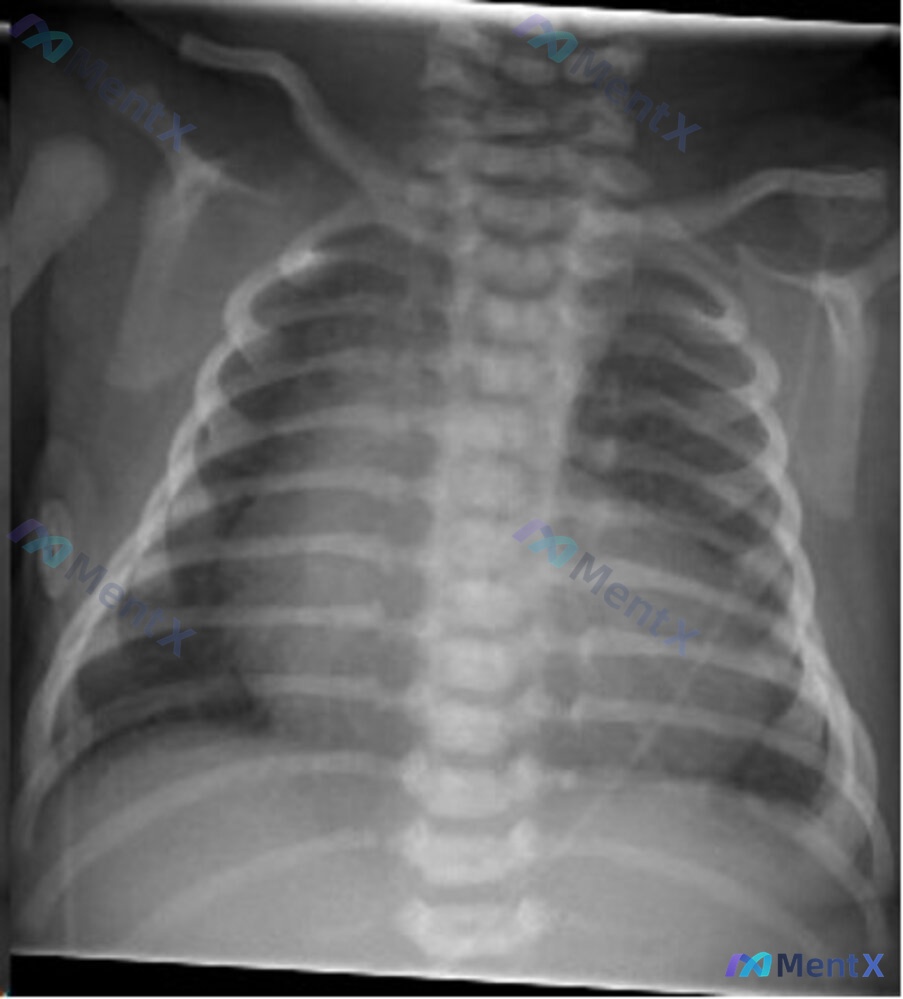

整理了一份儿科急诊病例: 16个月大男性患儿,无既往病史,因呼吸急促、呼气喘息、缺氧,5天内第二次送入急诊。 第一次就诊因鼻漏、发热、咳嗽,予吸鼻后出院;本次就诊母亲诉5天内出现呼吸加快、胸部收缩,生命体征:体温100.7℉,呼吸频率45次/分,氧饱和度90%。 问题来了:针对这个患儿,你认为最合适...